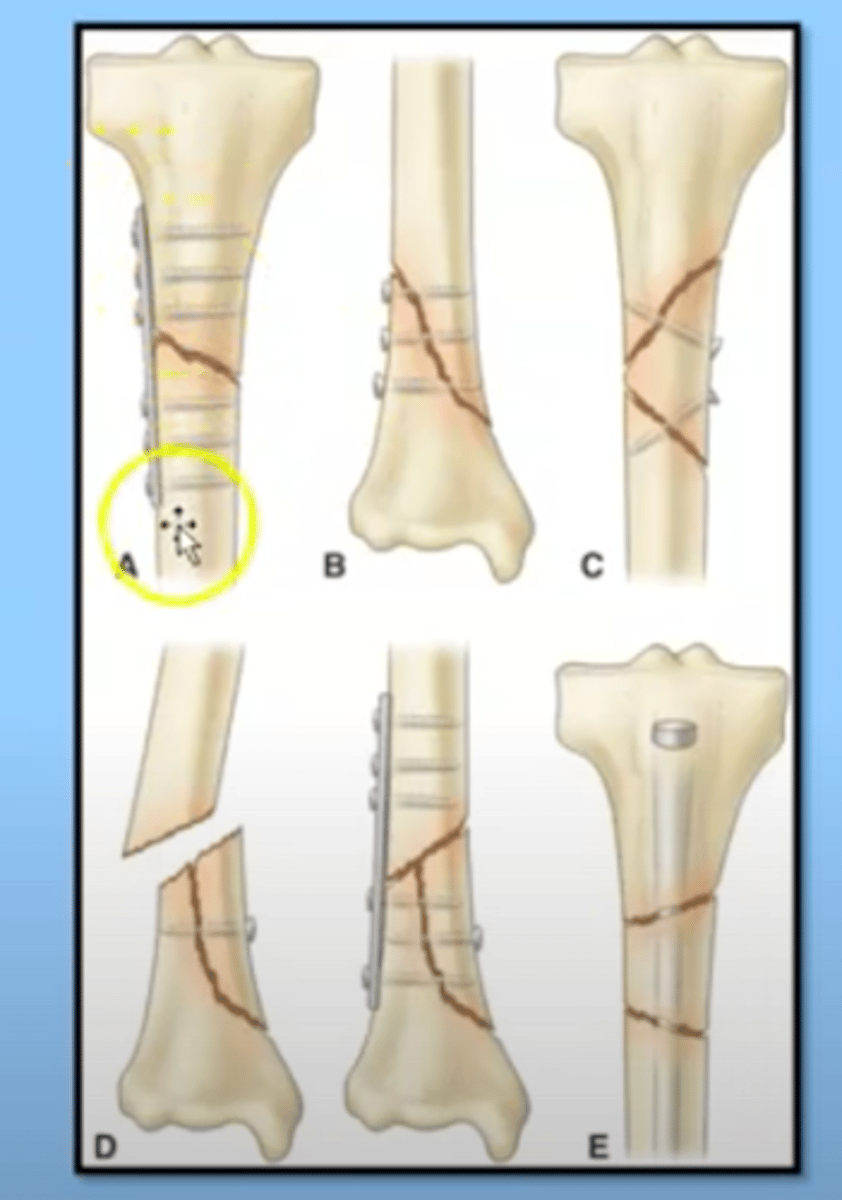

Medical management of fractures

Reduction

-closed

-open

Immobilization

-internal

-external fixation

-May require a surgical procedure to get the bone back in place and they have fixation (various devices, often screws or shafts that are put in place to maintain the bone in alignment so it can heal)

-some fixation devices are temporary, some permanent

open reduction

requires surgical intervention through the skin to get the bone back into place

internal immobilization

placed in surgery and the skin is closed over

external immobilization

the usage of devices that go right through the skin to immobilize